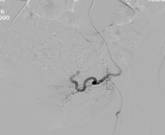

朱××,男,45岁,双侧股骨头坏死,左侧髋关节疼痛明显,不能独立行走,需使用止痛药物(图1,MR)。介入治疗术中造影(图2a)示:股骨头供血动脉分支稀疏,远端痉挛、股骨头骨质内无明显分支动脉血管;治疗后(图2b)造影见股骨头供血动脉分支血管明显增多,远端可见达股骨头骨质内,原髋关节疼痛消失,自行行走出院。

图1 图2a 图2b